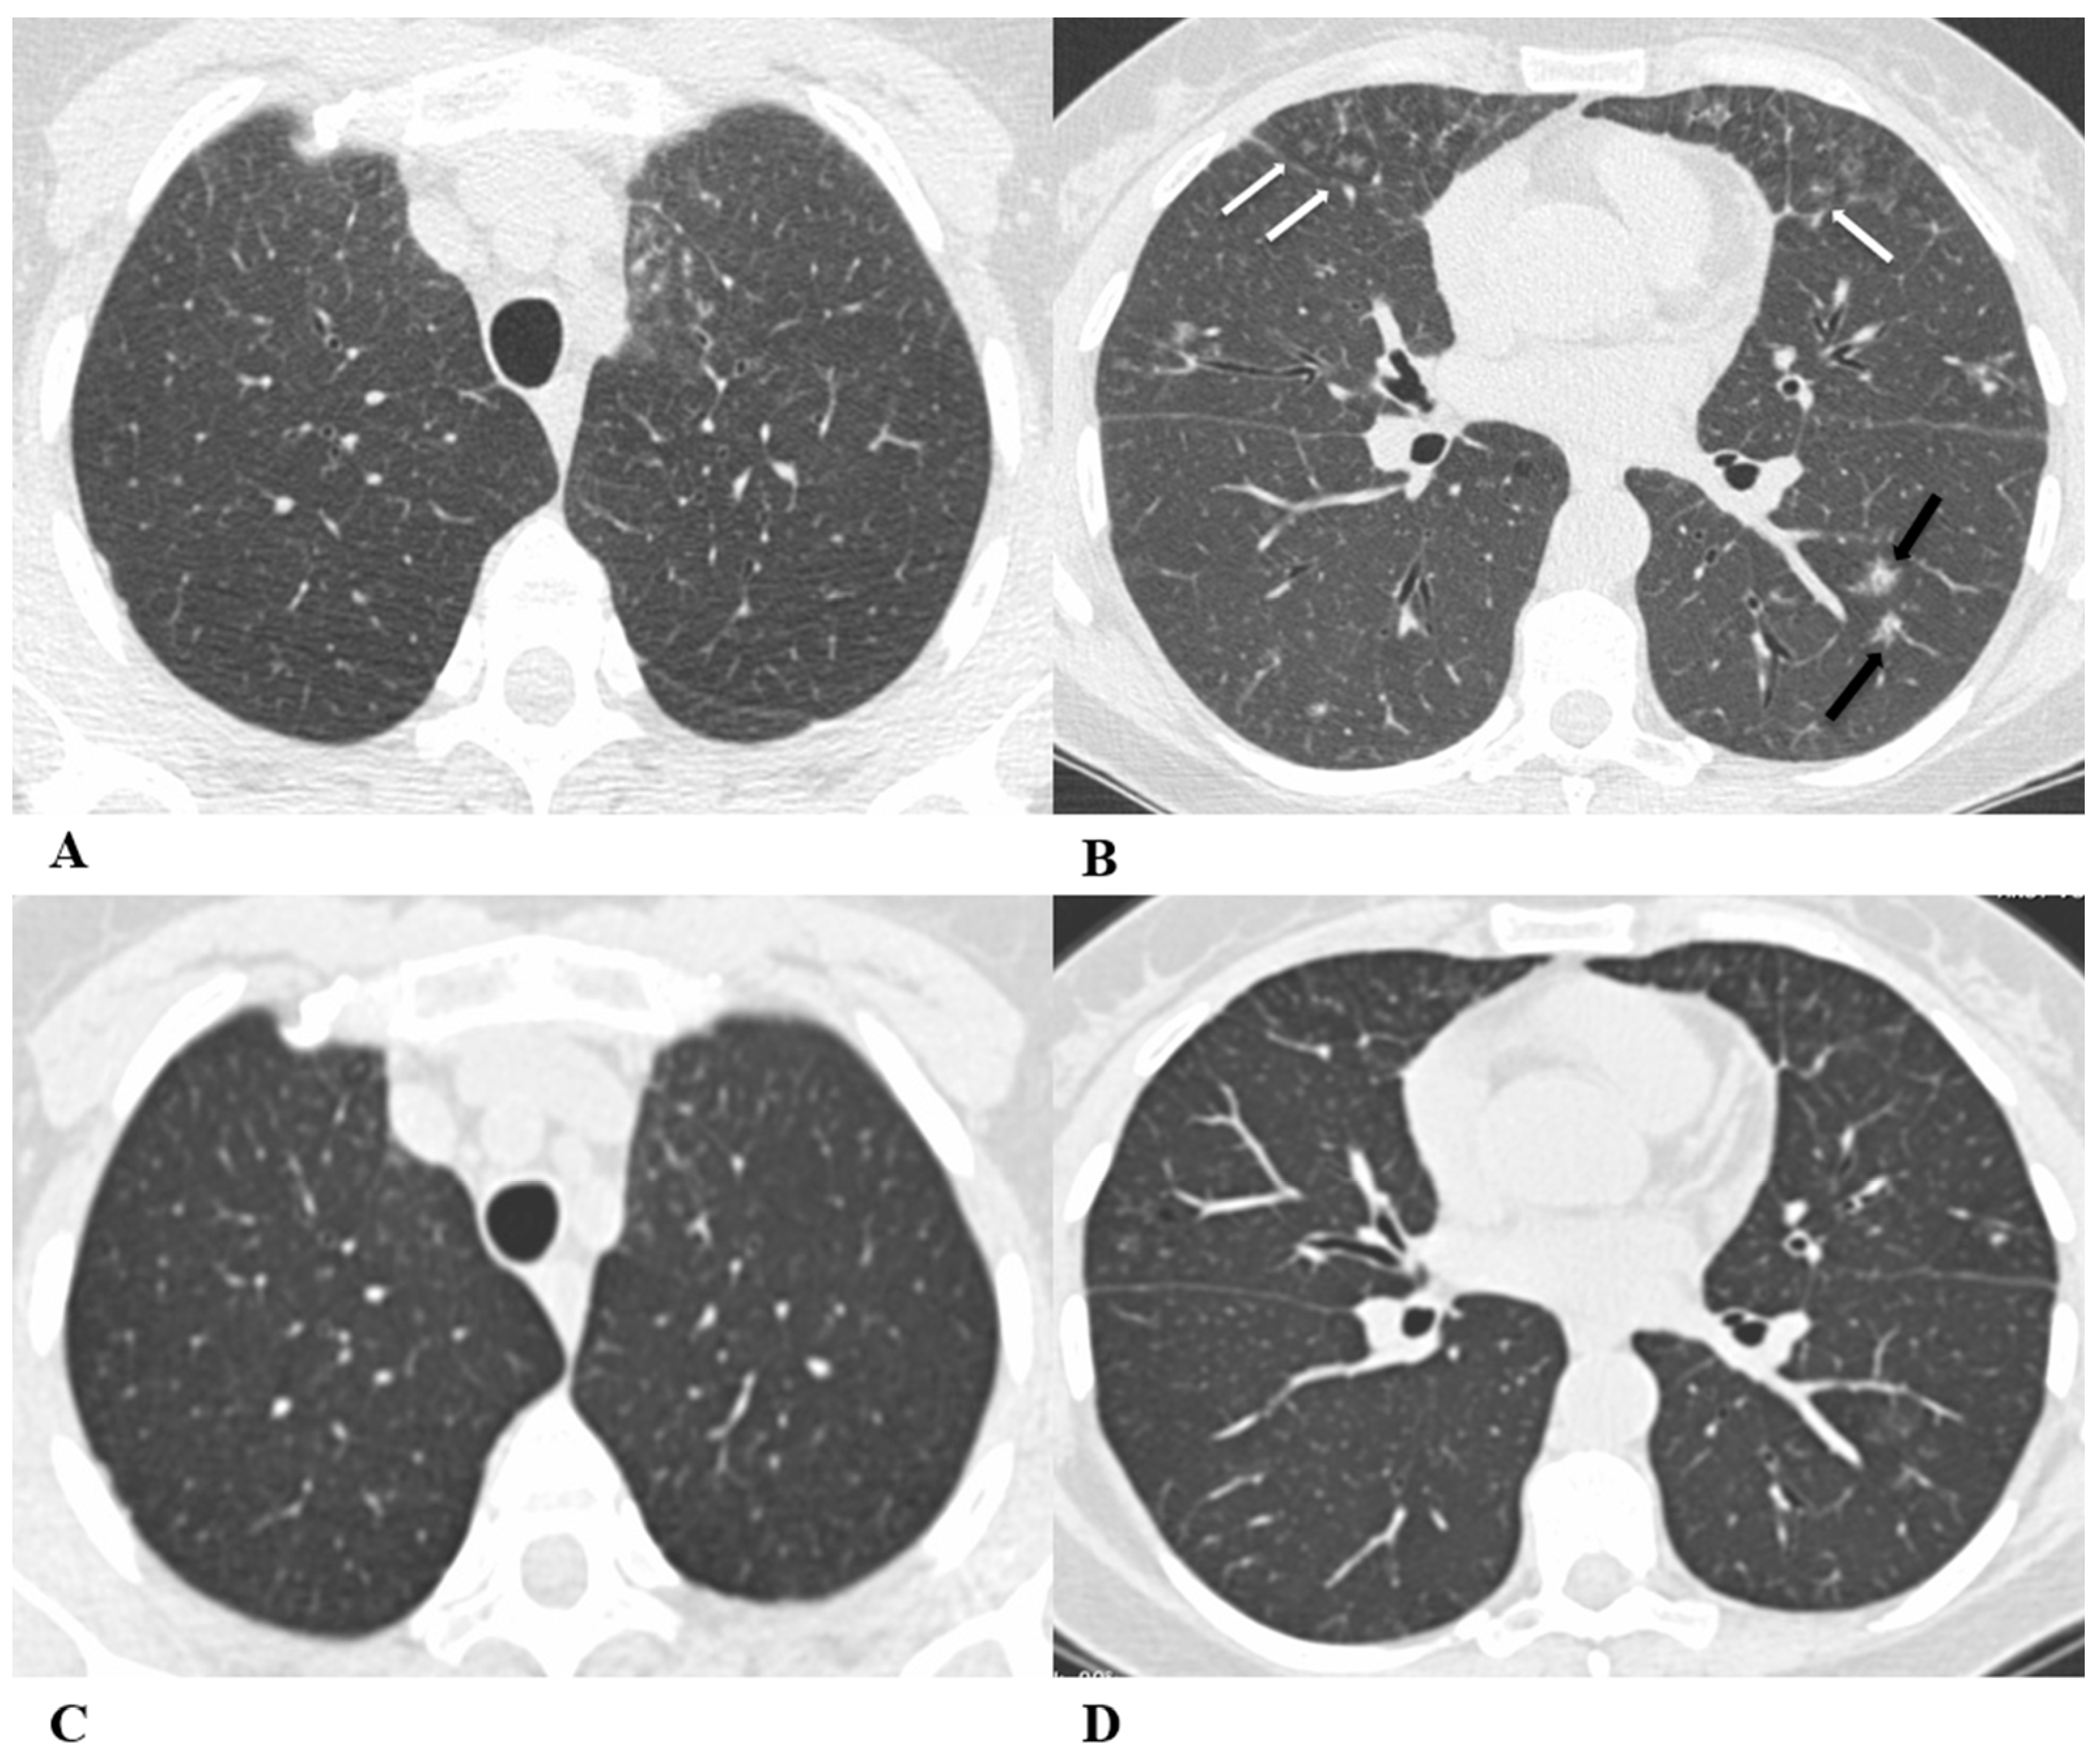

Figure 7.

Sarcoid-like reaction (SLR). A sarcoid-like reaction is a less-common non-pneumonitis irAE determined by the presence of non-caseating granulomatous inflammation in the lung parenchyma and lymph nodes, without criteria for systemic sarcoidosis [21].

Sarcoid-like reaction HRCT findings are represented in most cases by bilateral and symmetrical hilar and mediastinal lymphadenopathy, sometimes associated with peribronchovascular micronodules, peribronchial interstitial thickening and the infrequent coalescence of micronodules forming pseudo-masses with a predominantly dependent distribution. Lung parenchyma may be involved without adenopathy [11,13,22].

Bronchoalveolar lavage (BAL) shows moderate lymphocytic alveolitis, and its first-line treatment is with oral corticosteroids.

(A–D) A 75-year-old man with myelodysplasia and renal cell carcinoma. Fever, fatigue, cough and dyspnea affected the patient from the fifth month of treatment with pembrolizumab.

The axial chest CT image showed widespread micronodules with a miliary and perilymphatic distribution (A). Six days later, along with a moderate clinical worsening, the chest CT highlighted the development of large confluent areas in both lower lobes, with peripheral and declivous locations and the persistence of diffuse bilateral parenchymal micronodules (B); a mediastinal window of the same CT scan of image B demonstrated the volumetric enlargement of some lymphadenopathies in the sub-carinal station (white arrow (C)).

Chest CT performed 20 days later (D) after the discontinuation of pembrolizumab and treatment with oral steroids showed significant improvement in the pulmonary picture, with the complete resolution of the consolidations and a tendency towards the resolution of the bilateral parenchymal micronodulia.